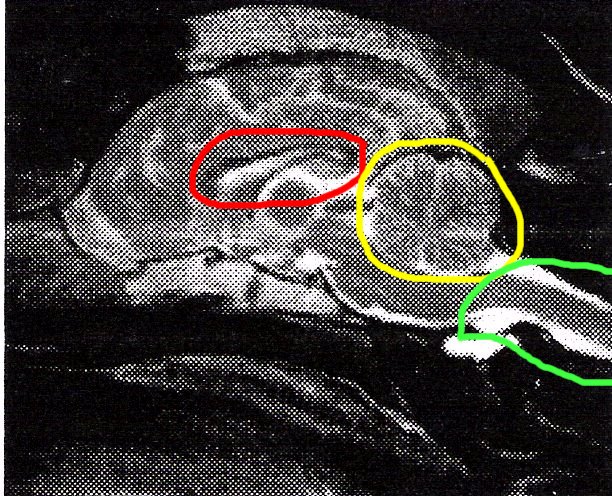

Above is a Cavalier with Syringomyelia (SM)

Red circle is showing enlarged ventricle in brain--hydrocephalus

(fluid inside ventricle)

Yellow is showing a severely squashed/pinched/compressed

cerebellum

Green is showing multiple syrinxes inside the spinal cord, one

quite large (the white is fluid)

Blue is showing a kinked/bent medulla-main part of the brain

stem